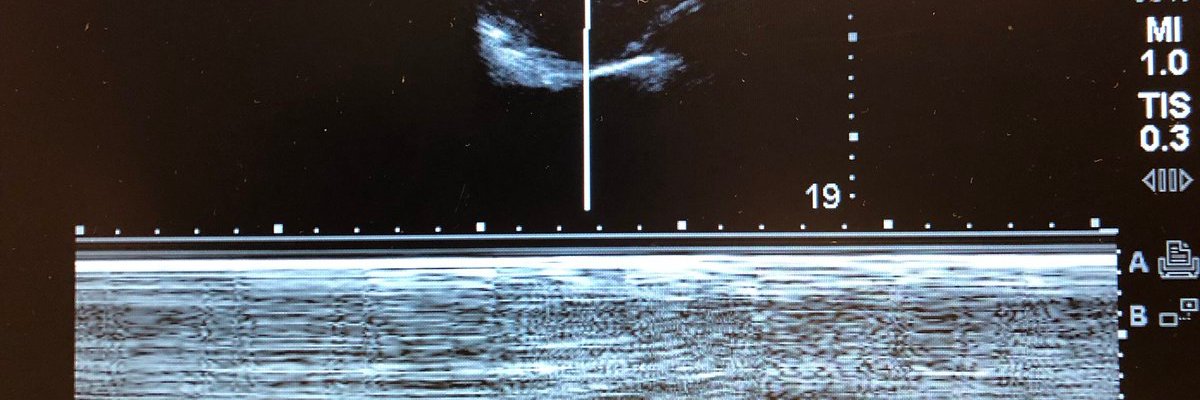

POCUS kan identifiera nedsatt diafragmafunktion postop

Patienter som genomgår thoraxkirurgi har ökad risk att få postoperativa komplikationer som beror på en nedsatt diafragmafunktion. Vissa ingrepp medför en ökad risk att skada n. phrenicus, medan andra medför en ospecifik fatigue av diafragma. En färsk studie från Italien visar att ”point of care ultrasound” eller POCUS under det första postoperativa dygnet är användbart för att upptäcka vilka patienter som har nedsatt diafragmafunktion och därmed är under ökad risk att få lungkomplikationer. Läs hela artikeln här: